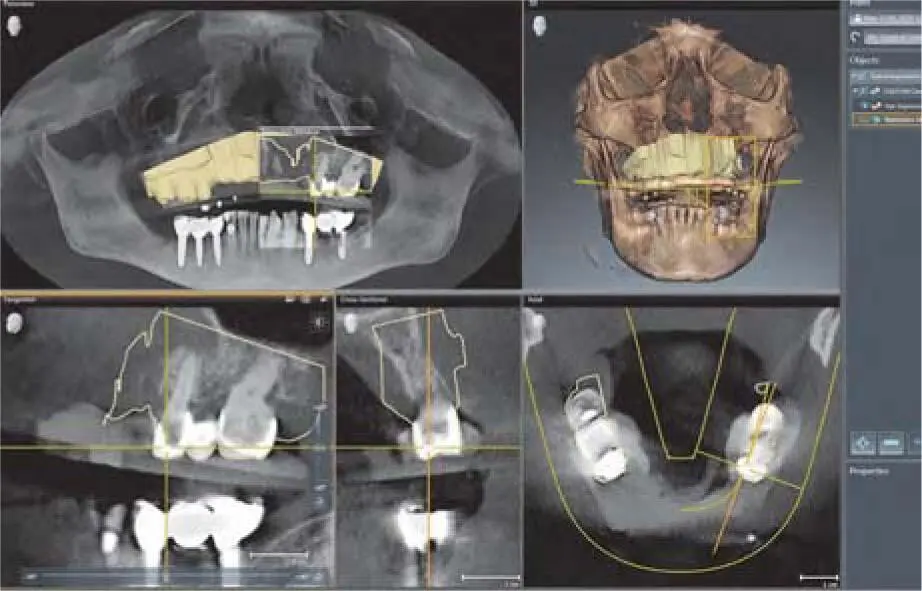

Fig 220bImporting the digital waxup into the implant planning software Sicat - фото 98

Fig 2-20bImporting the digital wax-up into the implant planning software (Sicat Implant 2.0; Sicat, Bonn, Germany).

Fig 220cSelection of marker point on residual teeth of the digital model and - фото 99

Fig 2-20cSelection of marker point on residual teeth of the digital model and corresponding structure within the CBCT to match the data sets.

Fig 220dControl of the contours of the optical model over the crowns of the - фото 100

Fig 2-20dControl of the contours of the optical model over the crowns of the corresponding teeth in the matched data set.

Fig 220eSelection of implant size abutments and sleeves for the detailed - фото 101

Fig 2-20eSelection of implant size, abutments, and sleeves for the detailed plan for simultaneous implant placement and lateral grafting.

Fig 220fDigital planning with volumetric samples of implant bodies and drill - фото 102

Fig 2-20fDigital planning with volumetric samples of implant bodies and drill sleeves in the position of the planned implants in the anterior maxilla.

Depending on the number of remaining teeth and the software used to accomplish implant planning, the prosthetic setup for implant placement can be performed using a radiologic template, or digitally by matching computer-assisted design/computer-assisted manufacturing (CAD/CAM) data. 68With this digital technique, it is possible to find the ideal position and direction of the implants in a simple way in relation to the ideal position of the implants and to fix them in a surgical guide ( Fig 2-20ato m). If necessary, the bone can be reconstructed in different directions according to the surgical guide.